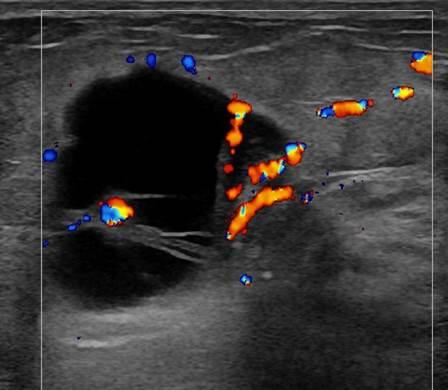

Ung thư vú

» Thông tin: Nữ giới – 55 tuổi.

» Lâm sàng: Khối tuyến vú.